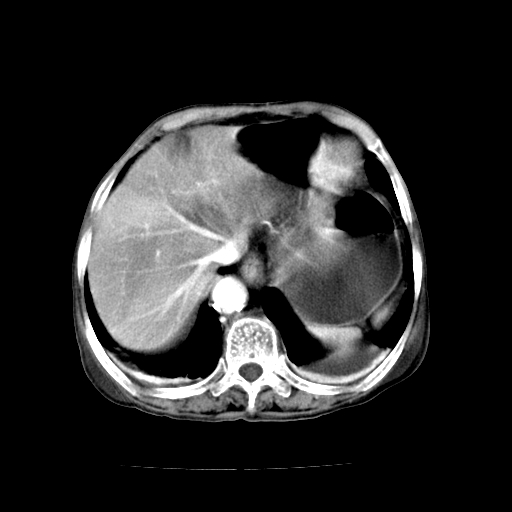

标题: CT19149:女,68岁,腹胀、恶心两周。 [打印本页]

女,68岁,腹胀、恶心两周,先做ct平扫,当时家属不同意强化,6天后家属要求增强扫描。

1、胃窦癌; 2、局灶性脂肪肝。

1、胃窦癌?建议行胃镜!; 2、局灶性脂肪肝。

1.局灶性脂肪肝;2.胃窦癌可能,建议行进一步检查。

1)胃窦壁厚,考虑胃窦癌?建议行胃镜检查。 2)局灶性脂肪肝。

支持考虑1、胃窦癌?建议行胃镜!; 2、局灶性脂肪肝。  3、双侧胸腔积液,胸膜增厚

不均匀脂肪肝,胃腔改变须结合钡餐或胃镜观察